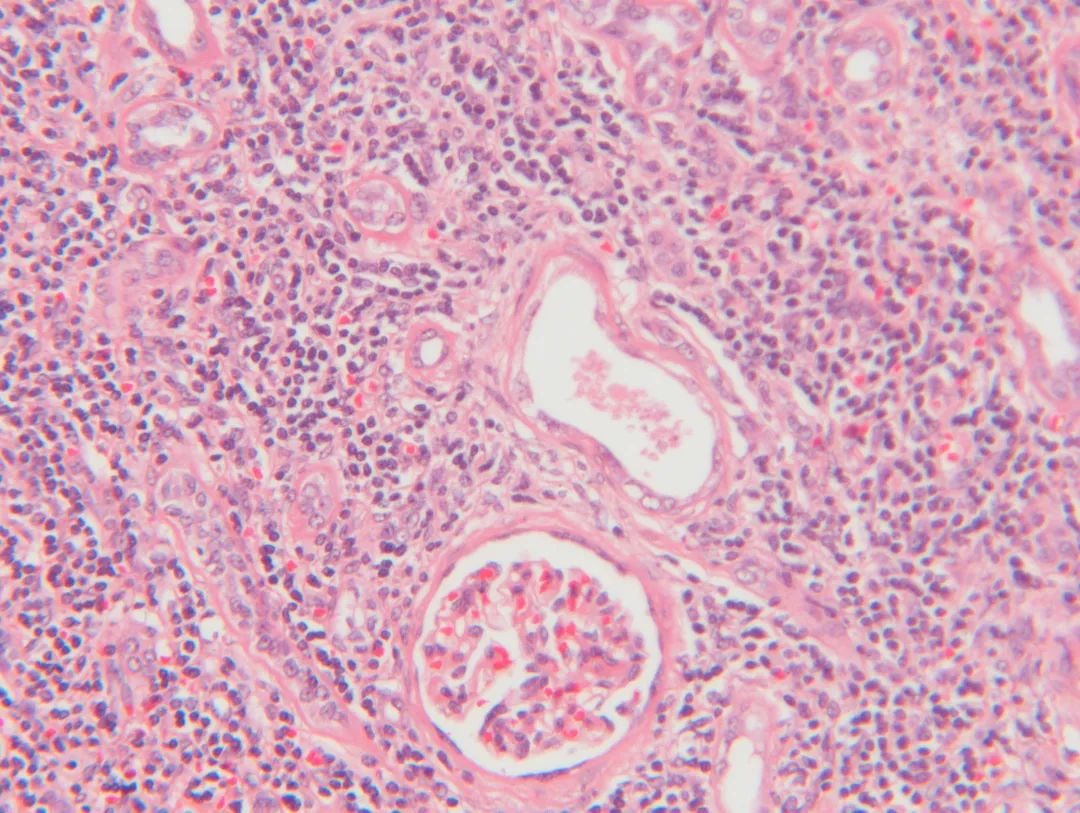

除了看肿瘤的生长速度和形态,临床最权威的判断方法是病理学诊断,它是肿瘤诊断的“金标准”。

病理诊断方法大体可分为组织病理、细胞病理,又可分为免疫组化病理和分子病理。通常临床医生会采用痰脱落细胞学检查、活体组织检查等细胞和组织病理方法对肿瘤进行形态学观察,结合其呈现的特征判断肿瘤的良恶性。如果在显微镜下难以观察,此时临床医生会通过免疫组化(IHC)以及荧光原位杂交(FISH)、聚合酶链式反应(PCR)、高通量测序(NGS)等分子病理方法做进一步诊断,借助蛋白、分子层面的生物标志物的指示,对肿瘤的良恶性做出准确的判断。

显微镜下观察到的组织病变